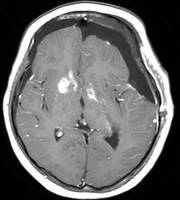

病例1:患儿男性,9岁。因反复出现意识丧失、视力下降半年收入院。入院后CT及 MRI显示颅内有形态不规则、“超大型”的颅咽管瘤,最大径约10厘米,见图1、图2。

图2.术前MRI

白色箭头指示肿瘤下极达枕大孔区